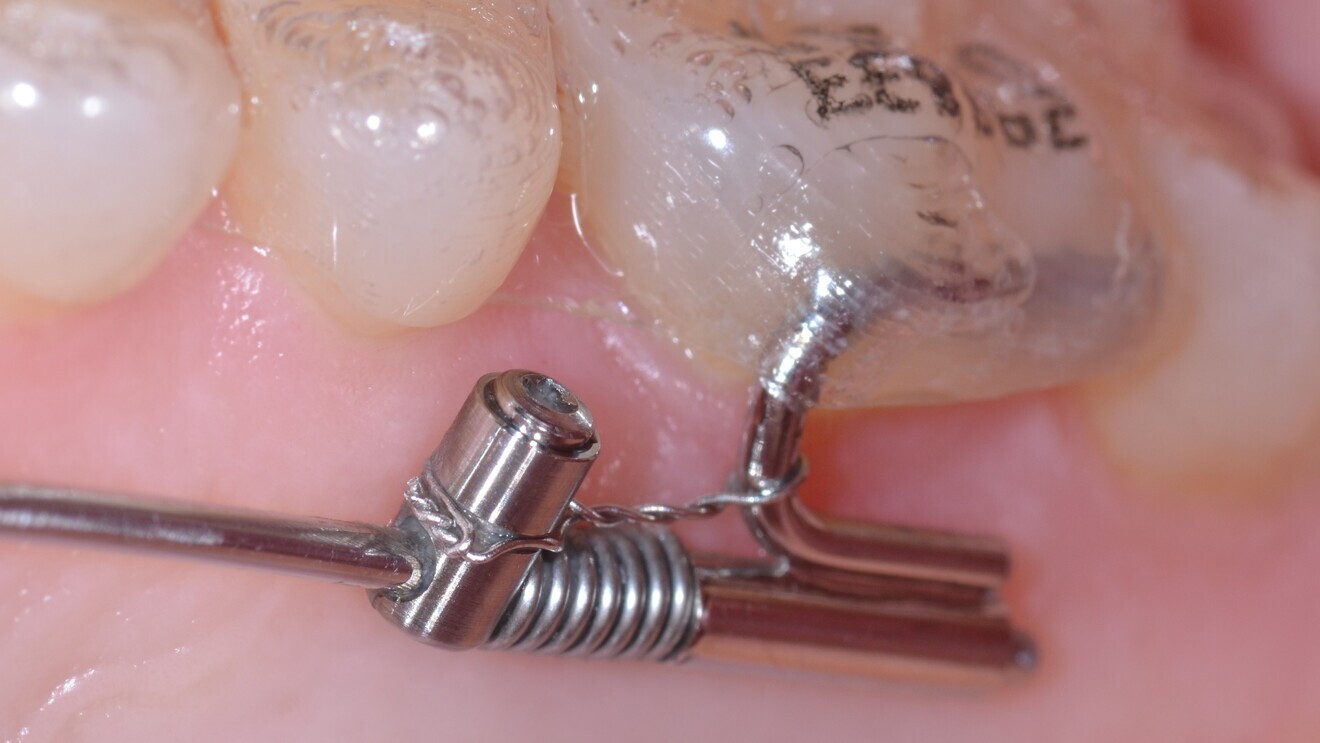

If clear aligners are to be used with a TAD-borne slider, the use of bonded tubes (Fig. 4) or metal-printed shell with attachments is recommended (Fig. 5).18 The advantage of bonded tubes or printed shells is that the adaptability and fit of the aligner is not undermined by the presence of stainless-steel molar bands. The aligner material can cover this bonded connection similarly to a large attachment (Fig. 4).

Fig. 4: Bonded tube for the connection from a Beneslider to a molar. After distalisation, the appliance should be left in situ for molar anchorage (made passive by using a steel ligature).